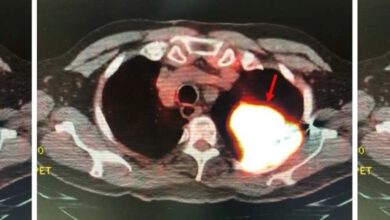

Выяснив это, исследователи выполнили поверхностную биопсию кожи спины у совпадающих по возрасту, полу и другим факторам онкологического риска пациентов онкодерматологической клиники. 11 из них интенсивно пользовались соляриями (от 50 до более 750 сеансов в прошлом), девять — не пользовались вообще. Такие же образцы нормальной кожи получены у шести трупов из общей популяции (они не являлись пациентами дерматологических клиник). Из всех этих образцов выделили отдельные меланоциты (всего 182 клетки) и в каждом из них секвенировали транскриптом и экзом.

Распространенность мутаций была почти вдвое выше в меланоцитах основной группы, чем в клетках контрольной (5,69 против 2,86 мутации на миллион пар оснований), число клеток с мутациями также было значимо выше. Анализ по анатомической локализации (верхняя или нижняя часть спины) дал схожие результаты. Также меланоциты пользователей соляриев чаще содержали патогенные мутации, способствующие онкогенезу (23 против 7,3 процента). Статистический анализ с помощью линейных моделей со смешанными эффектами с поправкой на анатомическую локализацию и статистические выбросы подтвердил значительно большее бремя мутаций в основной группе (p = 1,3 × 10−2), и эта связь сохранялась после исключения одного участника с исключительно большим количеством мутаций (p = 6,1 × 10−5).